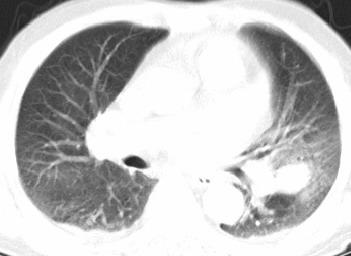

以下是引用xianxianzhongyi在2008-4-20 14:44:00的发言:[br]本人愚见:次病例短短两月的时间,呈现如此大面积实变,病变增长过于迅速,此其一。其二,病变在动脉早期既有明显强化。其三,左上叶后段及下叶背段多叶受累。其四,肺门及纵隔内未见明显肿大的淋巴结。估计层面较厚段支气管显示不清。 诊断:炎性实变可能性大。

以下是引用光影相伴在2008-4-20 14:39:00的发言:[br]支持:1)左侧中央型肺癌伴左肺上叶阻塞性肺炎。、[br] 2)双侧少量胸腔积液。